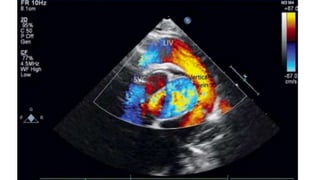

ECHOCARDIOGRAPHY

• Diagnostic and Investigation of Choice

• Important Observation

✦ PV not draining into LA

✦ Type of TAPVC

★ Cardiac - Dilated CS

★ Supracardiac - Dilated innominate vein and SVC

★ Infracardiac - Dilated IVC

✦ Insertion of Vertical Vein

✦ Narrowing of Vertical Vein

✦ Adequacy of ASD

✦ RA and RV Dilatation

✦ TR

✦ PAH

✦ RV Function

✦ Small LA

✦ LV size and Function

✦ PV Narrowing

✦ Size

✦ Doppler - Velocity > 2m/s

✦ Coexisting Congenital Defect

✦ VSD

✦ PDA